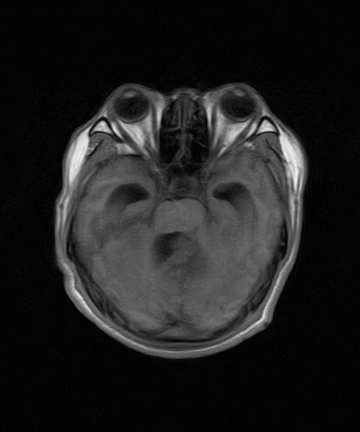

标题: MRI2064:少见病例。男性52,视力下降多年。 [打印本页]

标题: MRI2064:少见病例。男性52,视力下降多年。

四脑室区见混杂信号占位影,脑室系统扩张明显,临近结构显著受压称位,患者52岁,多考虑室管膜瘤可能性大

考虑第四脑室室管膜瘤并阻塞性脑积水。

考虑第四脑室室管膜瘤并梗阻性脑积水;部分性空蝶鞍;左侧上颌窦粘膜下囊肿。